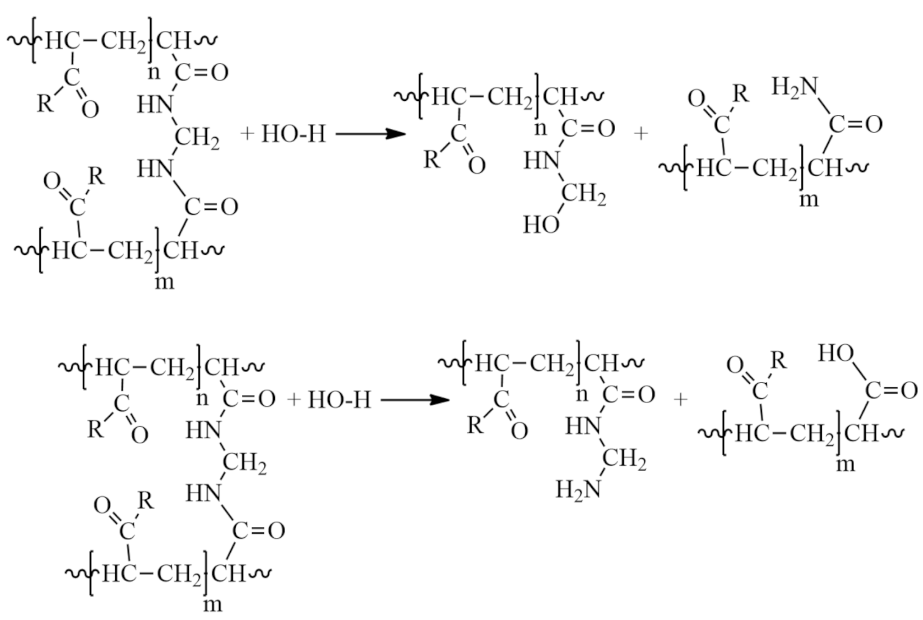

- Rupture of cross-linked chains. Nucleophilic effect of protonated solvent on cross-linked sections of macromolecules:

- Partial hydrolysis under slightly acidic conditions:

- The formation of partially or completely insoluble products due to the imidization reaction in acidic and slightly acidic media, leading to the formation of cyclic and three-dimensional spatial structures:

- Hydrolysis of the amide group in a slightly alkaline medium under the action of hydroxides and carbonates:

- Aminomethylation of PAA with aldehydes (formaldehyde, acetaldehyde, 5-hydroxymethylfurfural, malondialdehyde, fatty aldehydes, etc.) and primary and secondary amines in a slightly alkaline medium to form an aminomethylated polymer according to the scheme:

- The interaction of PAA with endogenous and exogenous aldehydes in acidic and slightly acidic media results in the formation of intramolecular cross-linking:

- In this case, intermolecular cross-linking can also occur, resulting in the formation of three-dimensional structures (-CONH-CH2-NHCO-):